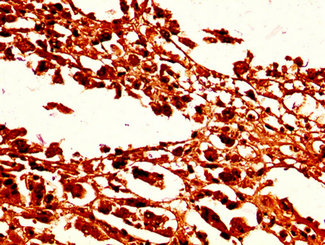

• IHC image of CSB-PA010378OA96nforHU diluted at 1:50 and staining in paraffin-embedded human melanoma performed on a Leica BondTM system. After dewaxing and hydration, antigen retrieval was mediated by high pressure in a citrate buffer (pH 6.0). Section was blocked with 10% normal goat serum 30min at RT. Then primary antibody (1% BSA) was incubated at 4°C overnight. The primary is detected by a biotinylated secondary antibody and visualized using an HRP conjugated SP system.